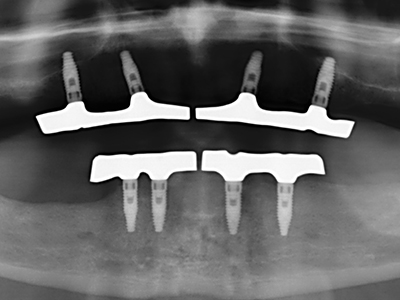

Die Präparation des lateralen Fensters bei der externen Sinusbodenelevation stellt gerade für chirurgisch unerfahrene Implantologen eine große Herausforderung dar. Die knöcherne Bedeckung der Kieferhöhle ohne eine Verletzung der darunterliegenden Schneider’schen Membran abzutragen ist dabei nur ein Teil der Operation – nach Schaffung eines ausreichenden Zugangs muss die Kieferhöhlenschleimhaut vorsichtig mobilisiert werden, um Raum für das einzubringende Material bzw. die Implantate zu schaffen. In dieser Indikation ist die Piezochirurgie zweierlei hilfreich: zum einen kann durch Verwendung diamantierter Instrumente eine selektive Knochenabtragung erfolgen und die darunter liegende Schleimhaut bleibt bei vorsichtiger Vorgehensweise intakt. Zum anderen unterstützen die Ultraschallfrequenzen zusätzlich eine komplikationslose Ablösung der Schleimhaut – sie werden durch spezielle stumpfe Ansätze in den Spaltraum zwischen Schleimhaut und Kieferhöhlenboden übertragen (Cassetta, Ricci et al. 2012, Pereira, Gealh et al. 2014) (Rickert, Vissink et al. 2013). So erscheint es nicht verwunderlich, dass in aktuellen Übersichtsarbeiten über die externe Sinusbodenelevation neben der Verwendung von rauen Implantatoberflächen und dem Einsatz von Knochenersatzmaterialien auch der Einsatz von piezoelektronischen Geräten als positiv bewertet wird (Wallace, Tarnow et al. 2012).

Wie sich in der Vergangenheit gezeigt hat stellt prinzipiell jeder knochenchirurgische Eingriff eine mögliche Indikation für die Piezochirurgie dar. So lässt sich die Präparation des mobilen Segmentes bei der Distraktionsosteogenese (Abb. 23-25) und der Sandwichosteotomie mit speziellen Ansätzen bewerkstelligen, ohne die für den Erfolg beider Techniken essenzielle Blutversorgung des krestalen Anteils zu gefährden (Gonzalez-Garcia, Diniz-Freitas et al. 2008).

Für die Entnahme von Implantaten ist die Präparation eines vestibulären Knochendeckels möglich, der nach Entfernung der Implantatschraube refixiert wird und auf diesem Wege die Kontur des Alveolarfortsatzes erhält.

Weitere Einsatzgebiete ergeben sich in der Kieferhöhlenchirurgie: Hier können nach konzentrischer Präparation eines in der Regel trapezförmigen Knochendeckels der fazialen Kieferhöhlenwand Pathologien und Fremdkörper aus der Kieferhöhle entfernt werden. Der Knochendeckel wird nach Abschluss des intra-antralen Operationsanteils reponiert und durch Verkeilen oder adaptierende Nähte gegen Dislokation gesichert.